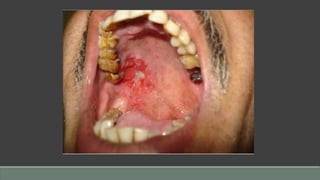

Erythroplakia

Etiology

• Unknown: a red patch that cannot be clinically attributed to another condition

• Contributing factors include tobacco use, alcohol consumption

Clinical Presentation

• Red, often velvety, well-defined patch(es)

• Most common on floor of mouth, retromolar trigone area, lateral tongue

• Usually asymptomatic

• May be smooth to nodular

• Chiefly in males

Diagnosis

• Appearance; history of tobacco/alcohol use

• Biopsy results differentiate from inflammatory and atrophic lesions

Differential Diagnosis

• Erythematous (atrophic) candidiasis

• Kaposi’s sarcoma

• Ecchymosis

• Contact stomatitis

• Vascular malformation

• Squamous cell carcinoma

• Geographic tongue/erythema migrans

Prognosis

• Fair to good depending upon microscopic diagnosis

• Almost all cases are premalignant to malignant upon initial discovery.

• Surgical excision if proven dysplastic/malignant